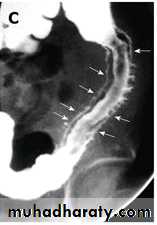

Main signs are strictures & mucosal irregularitya. The strictures (string sign) are variable in length (due to spasm of ulcerated loop or due to oedema & fibrosis of bowel wall) with proximal dilatation. When there is obvious disease of terminal ileum, the caecum may be contracted.

A long segment of narrowed ileum (string sign) is present with proximal ileal dilation& caecal contraction

TI

caecum

Two regions of high-grade stenosis are present in the proximal

small bowel.b. Ulcers may be deep +/- cobblestoning